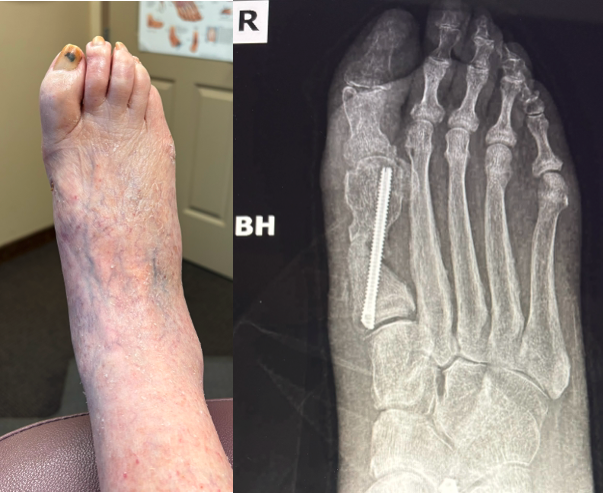

In Figures 3 A, B, C, D, the images depict the case of an elderly female who previously underwent a MIS bunion surgery. Unfortunately, she experienced a recurrent HAV and painful proximal hardware medially (Figures 3 A, B). She subsequently underwent hardware removal and revisional MIS bunion surgery (Figure 3 C, D).